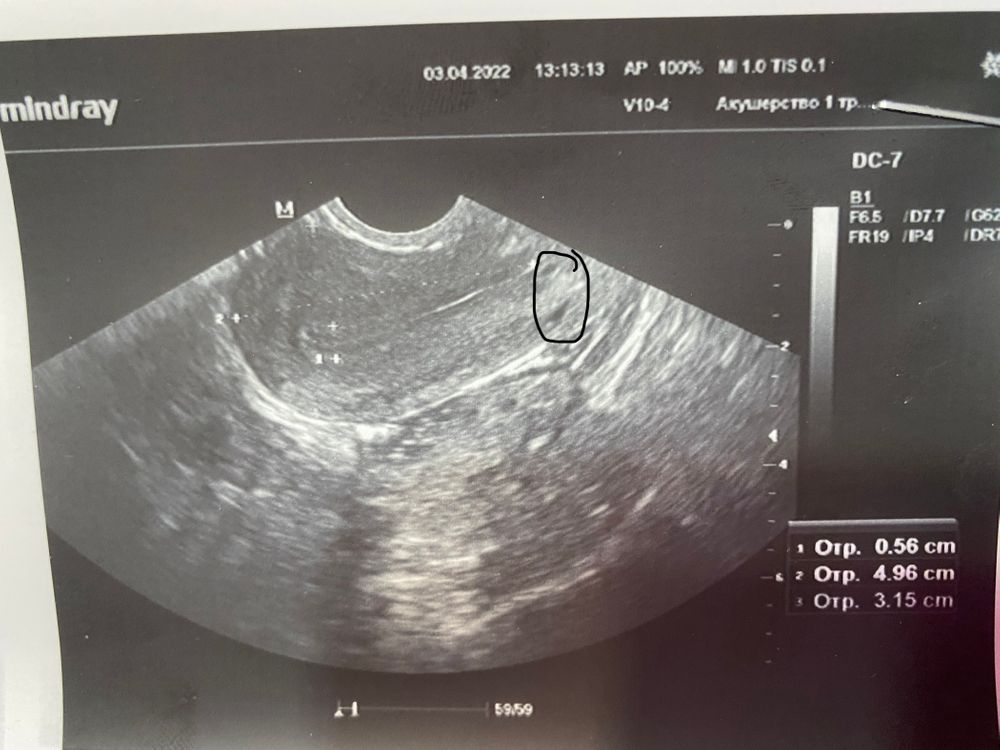

Месячные были полтора дня . Уже думала про бхб . Ведь сначала 2 день месячных был результат 16 хгч , через два дня сдала в инвитро там <1,20 …. Пошла на узи 10 дц Болит спина ,живот , грудь налилась . Завтра снова сдам хгч . А сегодня на узи в матке увидела чёрные точки . С узистом спорила она говорит ничего нет . Фото постараюсь добавить

Вы сами не видите что вы обвили? И вы ещё спорите с доктором 🤦♀️

То что вы обвели это почти шейка и внешняя часть матки которая находится в брюшную полость. Там ПЯ ну ни как чисто физически быть не может. И скорее всего это очаг аденомиоза

А эндометрий это полоска посередине, там должно быть ПЯ. И какое ПЯ вы хотите увидеть при отрицательном хгч?

И ещё у вас эндометрий не беременый, всего 5,6 мм. С таким не беременеют. Нужно выяснить причину тонкого эндометрия

Нет. Это не пя) у вас матка сомкнута, вон узенькая полоска выше и левее точки. Она прям как полосочка такая немного изогнутая. Такая продолговатая как будто краешки белые и внутри темнее.

Эта точка обведённая даже не в полости матки по снимку. И пя не так выглядит) да и хгч у вас не Б

В эндометрии у вас ничего нет, у вас это киста шейки матки, ниже точка аденомиоз может быть или миома и тд.